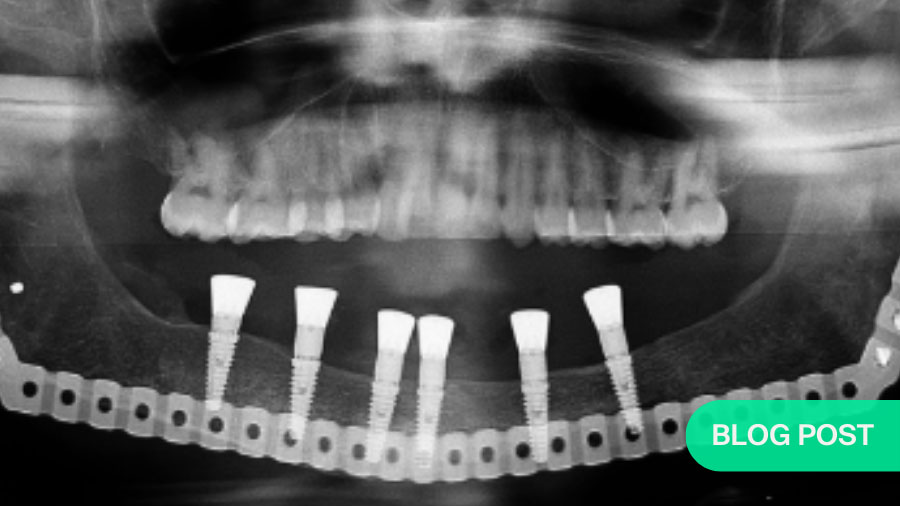

In contrast the particulate, compressed, autologous bone graft overcomes many of these challenges. Due to its mouldable properties it adapts to an arch and allows for the superior restitution of mandibular arch form and alveolar height (Figure 1), whilst significantly reducing patient morbidity and treatment costs.

This is particularly useful in children with large defects. An example of such a case illustrated below: CT scan of 10-year-old with large ameloblastoma (A). Panoramic radiograph (B) 13 years post reconstruction and 7 years post implant placement and dental rehabilitation. Patient grafted at age 10 with a composite graft of autologous bone and TGF-β3 loaded onto DBM (demineralized bone matrix).